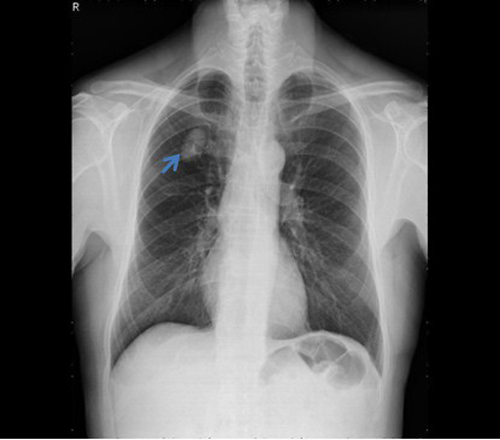

U phổi (mũi tên) trên hình chụp X-quang

Bác sĩ đã chỉ định chụp X-quang và CT ngực phát hiện bóng mờ đáy phổi trái. Khối u choán chỗ thùy dưới phổi trái, kích thước 25x27 mm.